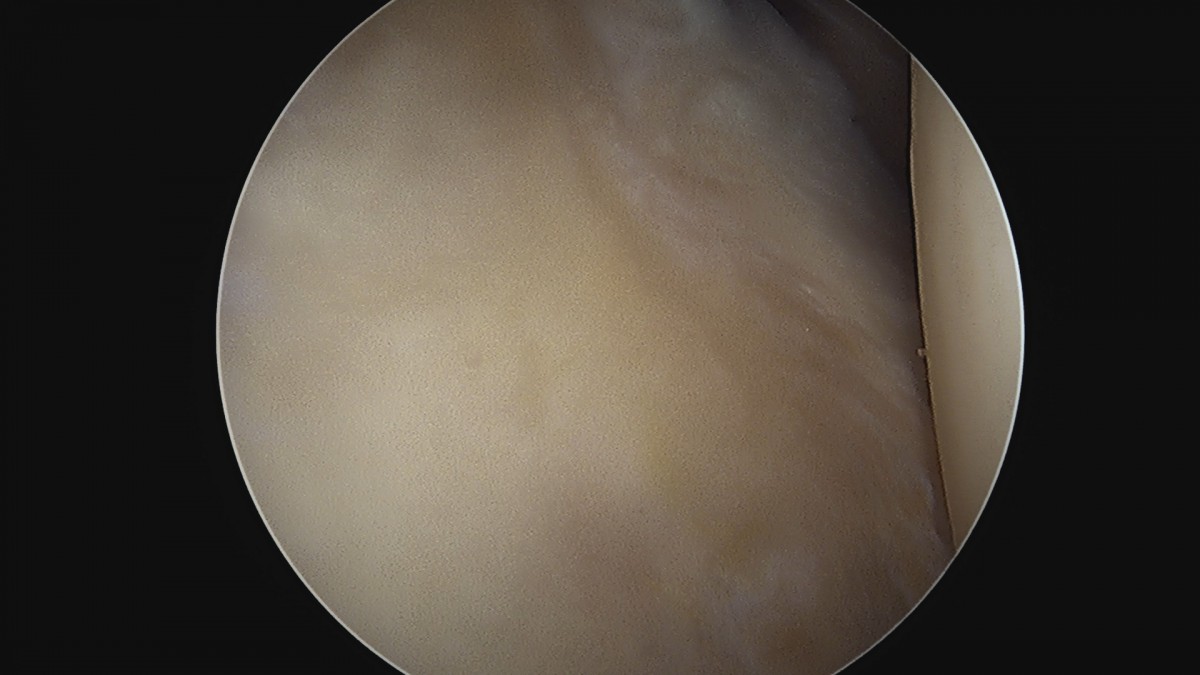

정지영원장님 어깨 회전근개 봉합술 임채O 환자

dae765e4d9ac96aee867c9d6292d8784_1758009114_2696.jpg